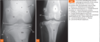

64

identify

incongruity too much space between the joint surfaces in all 3 images = elbow dysplasia